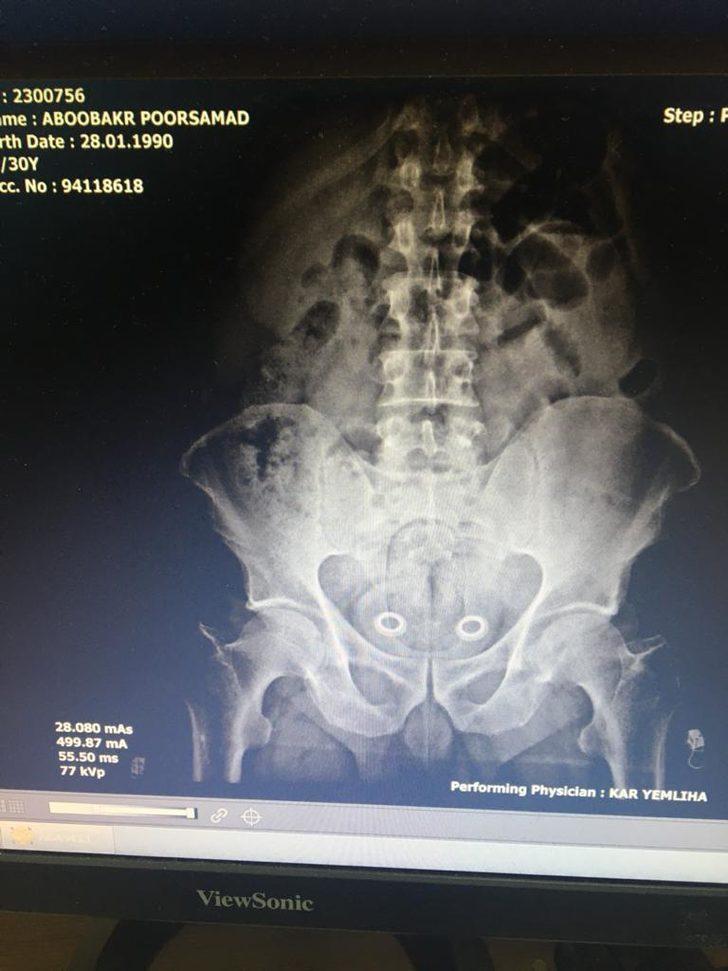

Bağırsağındaki uyuşturucu röntgende ortaya çıktı

Kars'ta, polis tarafından gözaltına alınan İran uyruklu şüphelinin çekilen röntgen filminde bağırsağında uyuşturucu taşıdığı ortaya çıktı.

İran uyruklu A.P. (47) ve N.Ş. (24) isimli kadın ile Türk vatandaşları Ö.A. (25), M.Y. (36) ve Ş.K. (34) gözaltına alındı. Araçta narkotik köpeği Odin’le yapılan aramada uyuşturucu bulunamazken bir adet tabanca ile 6 fişek ele geçirildi. İranlı şüpheliye götürüldüğü hastanede röntgen filmi çektirildi. Röntgen filminde, şüphelinin bağırsağında uyuşturucu taşıdığı belirlendi. İlaçla, İranlı'nın bağırsaklarındaki 110 gram metamfetamin ve 0,64 gram esrarı çıkarması sağlandı.

Şüphelinin narkotik köpeğine yakalanmamak için uyuşturucuyu bağırsaklarında gizlediği öğrenildi.